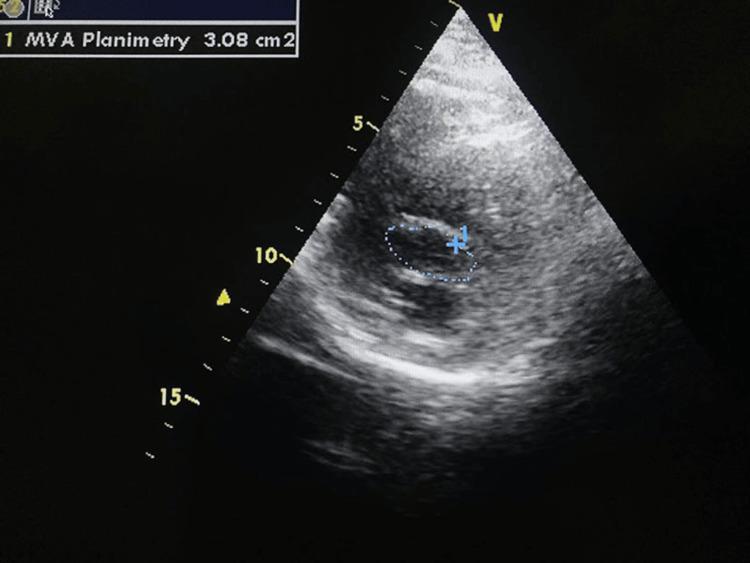

心房黏液瘤与风湿性二尖瓣狭窄:术前数天发生栓塞性中风

Atrial Myxoma and Rheumatic Mitral Stenosis: Embolic Stroke Strikes Days Before Surgery.

Cardiac myxomas are the most common primary cardiac tumors. Their primary location is the left atrium, but they can arise in any cardiac chamber. Although histologically benign, atrial myxomas are functionally malignant due to their high embolic potential, which can lead to severe complications such as ischemic stroke. Left atrial myxoma can mimic mitral stenosis by causing obstruction to the blood flow at the level of the mitral valve. In developing countries, rheumatic mitral valve is the most common cause of mitral stenosis, and the concurrent occurrence of mitral stenosis and rheumatic heart disease is a rarity. We present a case of a 43-year-old man diagnosed with both conditions who developed an ischemic stroke due to tumor embolization two days prior to planned surgical intervention. This case underscores the importance of timely diagnosis and management in patients with concurrent cardiac pathologies.

摘要